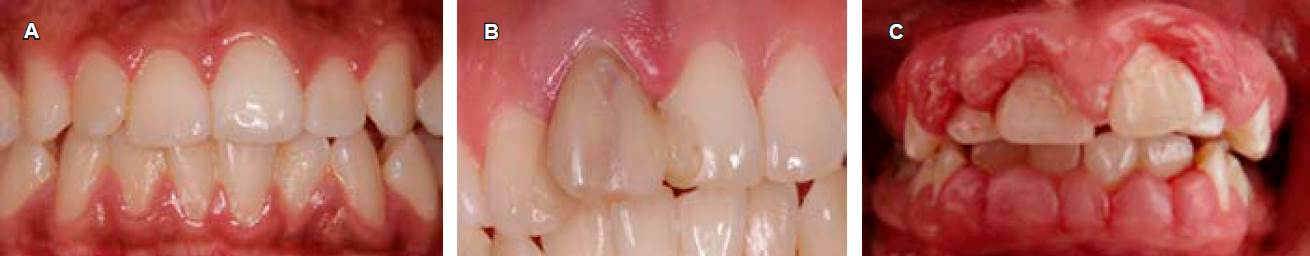

Los signos más comunes incluyen eritema, inflamación gingival, edema, sangrado y halitosis. La intensidad de los signos y síntomas clínicos varía entre los individuos, así como entre los sitios dentro de la dentición (Figura 3A).12

Figura 3 A) Gingivitis inducida sólo por biopelícula dental. B) Gingivitis mediada por factores de riesgo locales. C) Agrandamiento gingival generalizado severo influenciado por medicamentos (fenitoína).

Factores predisponentes: se definen como cualquier agente o condición local que contribuye a la acumulación de biopelícula dental (anatomía dental, posición del diente, restauraciones) (Figura 3B).

Para ser considerado un agrandamiento gingival inducido por medicamentos, el tamaño debe ser mayor de lo que normalmente se esperaría de una reacción inflamatoria en los tejidos gingivales; al igual que la gingivitis puede clasificarse por extensión y severidad (Figura 3C).